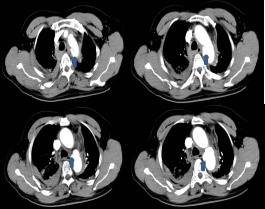

外院胸部CT:主动脉壁增厚

主动脉CTA:主动脉弓降主动脉处破口,近端破口直径约7.6mm

我院心脏大血管外科葛圣林、冯俊波两位主任立即赶往手术室,为谢先生行主动脉夹层腔内隔绝术,术中造影见主动脉血肿持续增大,血压心率极不稳定。葛圣林主任即刻植入覆膜支架封闭破口,谢先生的生命体征立即稳定下来,两小时后清醒。术后第一天,拔除气管插管,术后第二天就返回了普通病房。